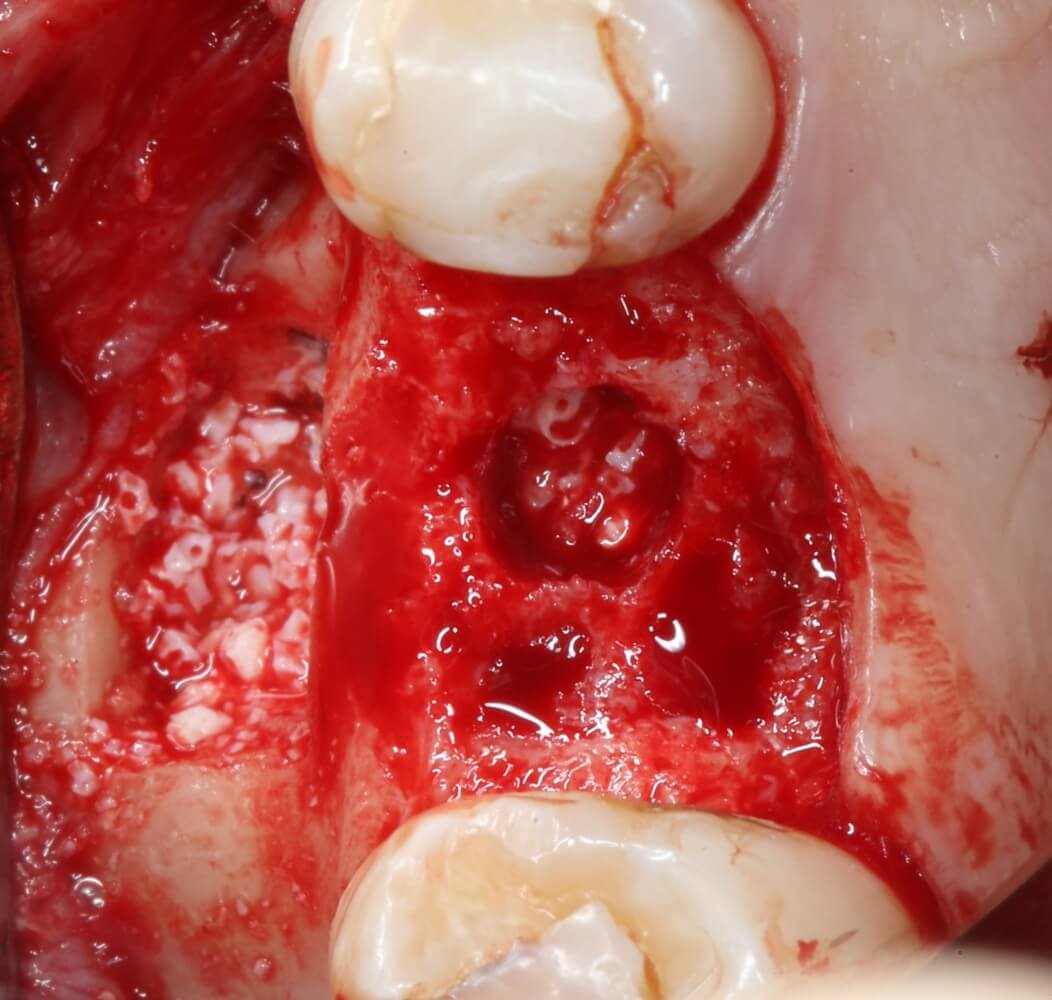

В общем, мы с вами не придурки слесари-столяры, периимплантита не хотим, поэтому кортикальные фрезы не игнорируем:

Кортикальная фреза погружается строго до отметки (см выше). В нашем клиническом случае (с синуслифтингом) это особенно важно, чтобы имплантат не улетел в субантральное пространство. Таким образом получаем лунку, полностью конгруэнтную будущему имплантату. Это очень-очень важно:

Пришло время вернуться к синуслифтингу и заполнить сформированное ранее субантральное пространство графтом (Geistlich Bio-Oss Pen):